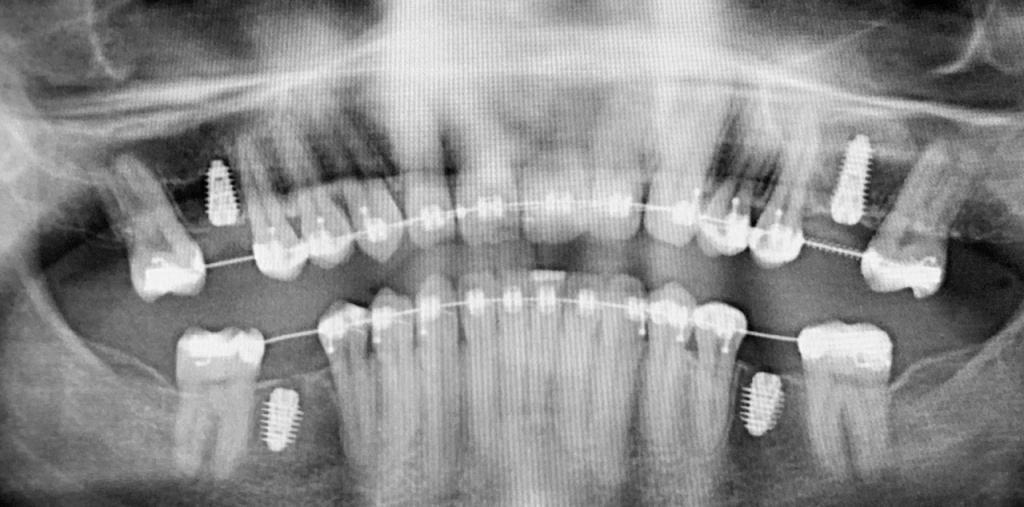

По результатам диагностики принято решение провести синус-лифтинг с помощью боров SinPro. В ходе вмешательства установлены имплантаты AnyRidge и AnyOne с первичной стабилизацией 40 Ncm.